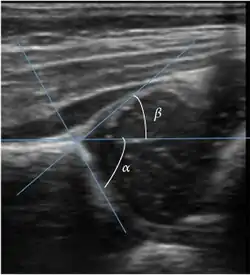

Ultrasound is the first-choice technique for diagnosis of newborns hip dysplasia. In experienced hands with appropriate technology, ultrasound can also be useful during the first year of life. Some European healthcare systems encourage universal ultrasound screening in neonates between the sixth and eighth weeks. Although it shows higher initial costs caused, it leads to significant reduction in the total number and overall costs of dysplastic hips undergoing operative and nonoperative treatment.[1]

Ultrasound allows categorizing pediatric hips, according to Graf’s criteria, in four main types: normal, immature, and dysplastic (subluxed and dislocated). This classification is based on measurements of the acetabular inclination angle (alpha), cartilage roof angle (beta), and infant age. The femoral head coverage can also be determined by dividing the length of the femoral head covered by the acetabular fossa and the diameter of the femoral head. Its lower normal limits are 47% for boys and 44% for girls (Figure 11).[1]

Figure 11: